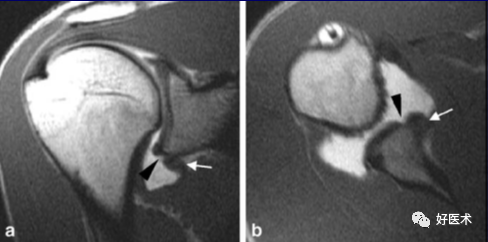

(1)盂肱关节前部不稳定

常见病因:创伤,多见于运动员(当手臂处于外旋、外展位)

一般累及盂唇及韧带,尤其是前下盂肱韧带复合体(前下盂唇与下盂肱韧带前束组成),盂肱韧带在其中部撕裂或附着于肱骨处撕裂。

1.Bankart lesion

盂肱下韧带和前盂唇(前下盂唇韧带复合体)从关节盂边缘撕脱,伴肩胛骨骨膜的撕裂。首次损伤后不恰当愈合可导致反复肩关节不稳。

2.Bony Bankart lesion

前下盂唇韧带复合体从关节盂边缘撕脱,伴继发于前关节脱位的肩胛盂骨性骨折。

3.Perthes lesion

Bankart lesion的变异:前下盂唇韧带复合体从关节盂边缘脱离,但骨膜完整且向前内侧剥脱,因此盂唇可在正常解剖位置。

4.前盂唇韧带骨膜袖撕脱

多见于反复脱位的患者。类似于Bankart 损伤,但其肩胛骨前骨膜保持完整,MR 关节造影显示对比剂出现于盂唇与肩胛骨关节盂之间,而骨膜完整连于肩胛盂 。

需与关节盂唇的变异鉴别。

6.盂肱韧带肱骨附着部撕脱(HAGL)

关节囊与肱骨交接处不连续;

冠状位上关节囊呈”J”形改变;

T2横轴位肱骨交界处水肿出血;

许多病例合并Hill-Sachs损伤。

少见,多发生于橄榄球、冰上运动等接触性体育的运动员,只能依靠关节造影发现。

(2)盂肱关节后部不稳定

仅占肩关节不稳定的2~4%

肱骨头常向后半脱位

在后盂唇发生破裂或粉碎时应考虑该病

MRI关节造影示:造影剂向后方在后盂唇、关节囊和冈下肌间渗出。

盂唇退变,致盂肱关节多方向不稳